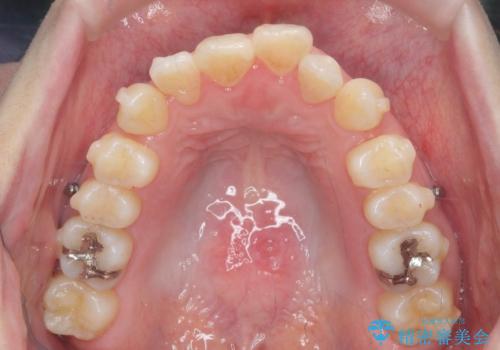

咬合関係の改善、前歯の角度、がたつきを改善するため、マイクロインプラントを用いて上顎の奥歯を後方へ移動させていきます。

矯正治療後、前歯のがたつき、咬合関係が改善され満足いただくことができました。